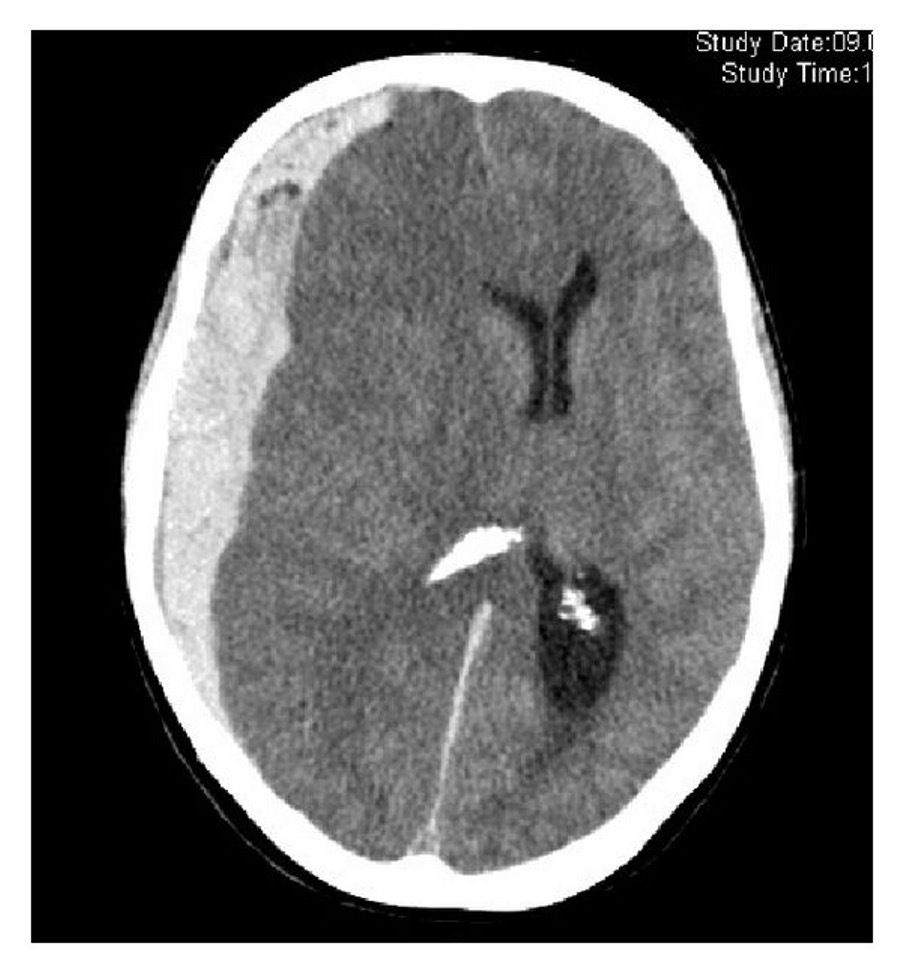

32

**IVH** - On CT imaging it appears as hyperdensity within the dark CSF spaces within the ventricles.

**Intraventricular haemorrhage**: hyperintense (bright) blood within the ventricles (with a fluid level); may be **primary**: started in ventricles or **secondary**: extension of extra-ventricular bleed (usually SAH or intracerebral e.g. basal ganglia)

Basal ganglia bleed